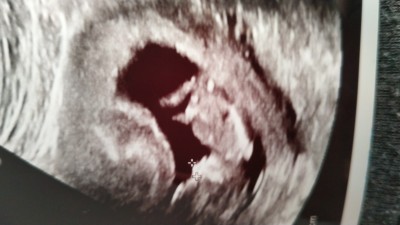

12+2 yüz doktor cinsiyetini gördü ama söylemedi sizce nedir

Gebelik haftası 12+2

Erkeğe benziyor

Sanki bacakalrinin arasında bir çıkıntı var gibi

Kiza benzettim cnm

Kız benziyor